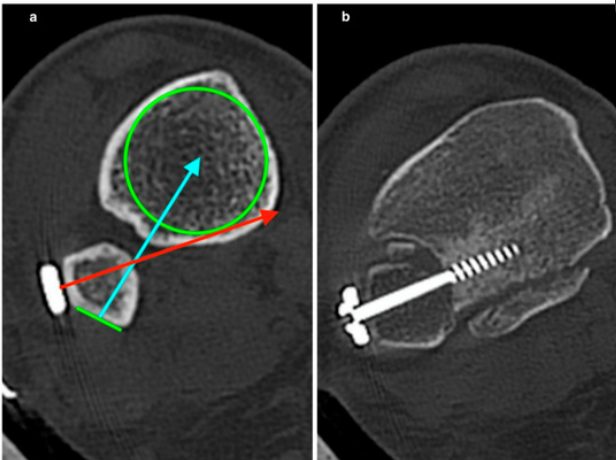

Рис. 14. Положение малоберцовой кости в боковой проекции

КТ превосходит стандартную рентгенографию в оценке целостности синдесмоза и способна выявлять подвывих синдесмоза, которую сложно визуализировать на обзорных рентгенограммах, особенно в неочевидных случаях. Возможность оценки обоих голеностопных суставов делает КТ предпочтительным неинвазивным методом оценки репозиции синдесмоза.

КТ-сканирование синдесмоза обычно проводится на уровне наиболее выступающей точки переднего бугорка большеберцовой кости. Повреждение синдесмоза диагностируется при межберцовом промежутке более 6 мм или расширении более 2 мм по сравнению с контралатеральной стороной. Повреждение с расхождением 2–3 мм может быть подтверждено на фронтальных КТ-срезах.

Рис. 15. Тибиофибулярная линия Гиффорда (TFL) на аксиальных срезах КТ и МРТ. Линия проводится вдоль переднелатеральной кортикальной поверхности малоберцовой кости. Расстояние от переднего бугорка Тилло-Шапута до TFL не должно превышать 2 мм. Параметр чувствителен к ротационной нестабильности.

КТ с нагрузкой (weight-bearing CT, WBCT) обладает дополнительным преимуществом — динамической оценкой синдесмоза: при нагрузке выявляются значимые латеральная трансляция и наружная ротация малоберцовой кости относительно вырезки.